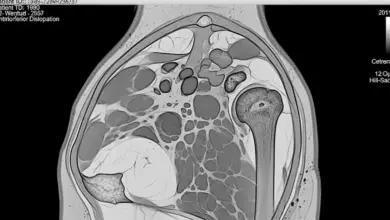

Prótese de ombro (artroplastia) é a substituição parcial ou total da articulação por componentes artificiais.

- Fraturas complexas em que reconstruir não entrega estabilidade.

- Necrose da cabeça do úmero.

- Artropatia do manguito rotador (quando a lesão é antiga, extensa e não tem reparo confiável).

- O que os exames mostram: radiografia ajuda a entender artrose e deformidades, ressonância avalia tendões, labrum e músculo. Em alguns casos, tomografia é decisiva para planejar a prótese.